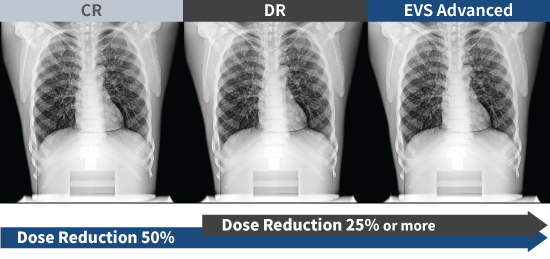

EXPRIMER Advanced Series proporciona una alta calidad de imagen con un 50 % menos de dosis que CR y un 25 % o más de dosis reducida en comparación con DR.

Experimente la reducción de la dosis del paciente

La dosis reducida para el paciente se logra a través del potente rendimiento de dosis baja de EXPRIMER Advanced Series.